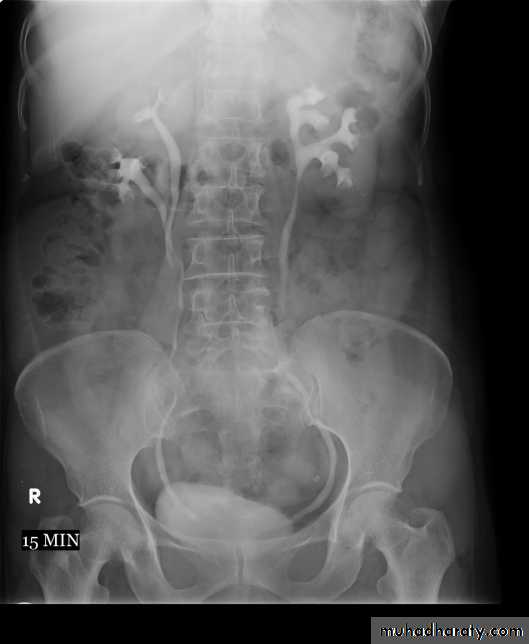

2. Pyelogram Phase(l-5 minutes after injection of contrast) .3. After 10 minutes with compression, to get better distention of the pelvis and calyces.

4. Full length film after release of compression .